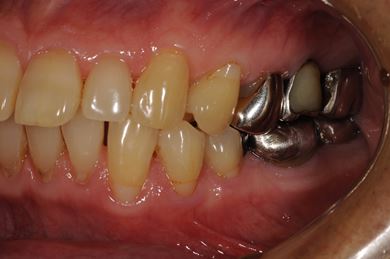

インプラントの症例写真 IMPLANT

| 性別/年齢 | 男性 / 57歳 | ||||||||||||||||||||||||||||||||

| 主訴 | 右奥歯のブリッジが取れ、支柱の2本の歯が痛むため、インプラント治療を希望。 | ||||||||||||||||||||||||||||||||

| 治療内容 | インプラント2本、ハイブリッドセラミック2本 | ||||||||||||||||||||||||||||||||

| 総治療費 | 533,610円 | ||||||||||||||||||||||||||||||||

| 治療期間 | 1年0ヶ月 |